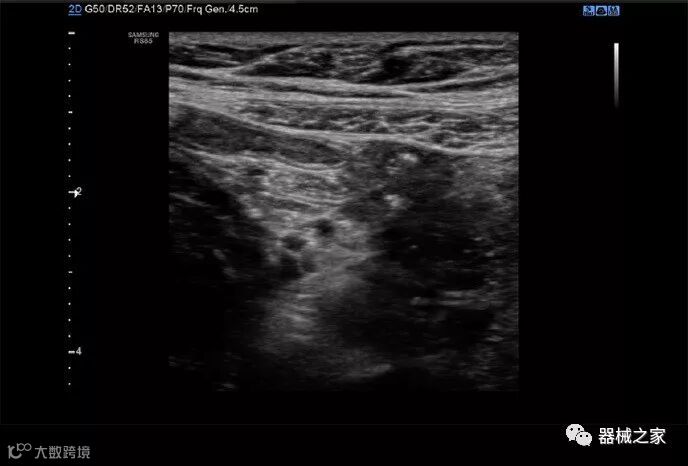

三星RS85超声系统于2018年获得FDA批准,其设计目的是将许多多步骤操作组合成一个步骤,以减少击键和重复的用户交互。

在几年前,超声波无法对小型慢流血管中的血流进行成像,但现在有少数供应商提供具有此功能的系统。该特征提供了另外一种检查病变以指示癌症或炎症的方法。其中一个是佳能Aplio 900 CV系统,它可以显示毛细血管中的血流量。日立的Arietta 65中程系统提供了一种可视化小血管的功能,可以更好地观察肾脏等器官的灌注情况。三星RS85还提供MV-Flow可视化慢流微血管结构。